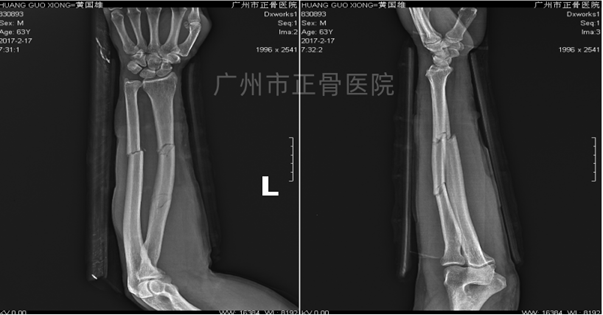

X线片检查结果:左侧桡尺骨双骨折,其中桡骨为多段骨折,位线尚可;尺骨骨折远端向下移位,向桡侧成角。

▲复位前,骨折明显成角移位

▲复位后,骨折对位对线良好